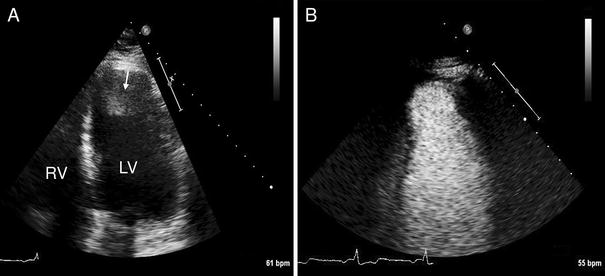

Assessment of an intracardiac thrombus using CEUS. A 61-year old man with a history of a large apical-anterior myocardial infarction was referred for echocardiography for the evaluation of cardiac thrombus. a Standard echocardiography (apical 4 chamber view) demonstrates an abnormality in the left ventricular apex which was a suspected thrombus (arrow). b CEUS demonstrates that there is actually no thrombus in the left ventricular apex. The abnormality that was observed on standard echocardiography was probably a reverberation artefact